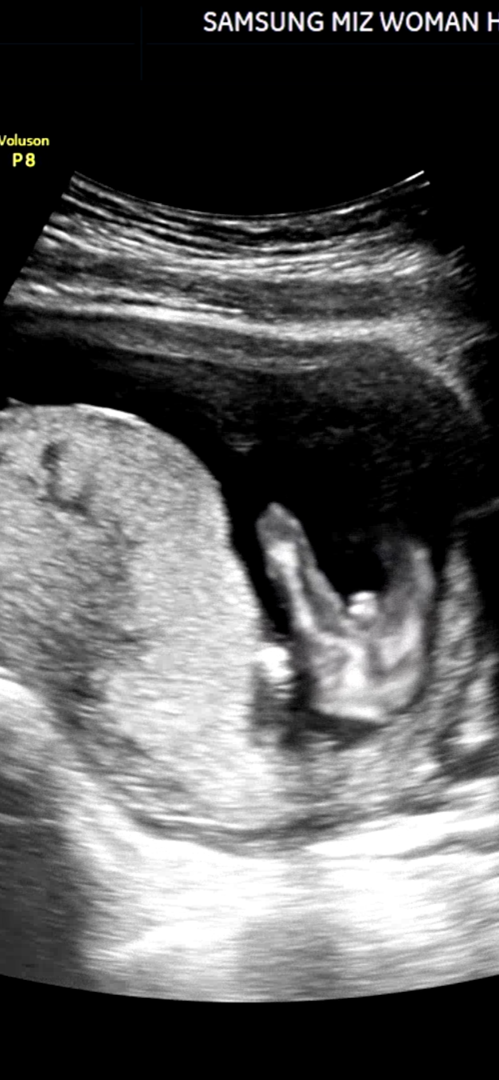

14주 3일 성별반전

안녕하세여! 오늘 성별보구 왔습니다! 이정도면 성별반전 없게쬬???

아들은 반전이 없다고들 하던데요ㅋㅋ저희 아기도 14주에 저랬는데 반전없이 16주차 아들이네요😊